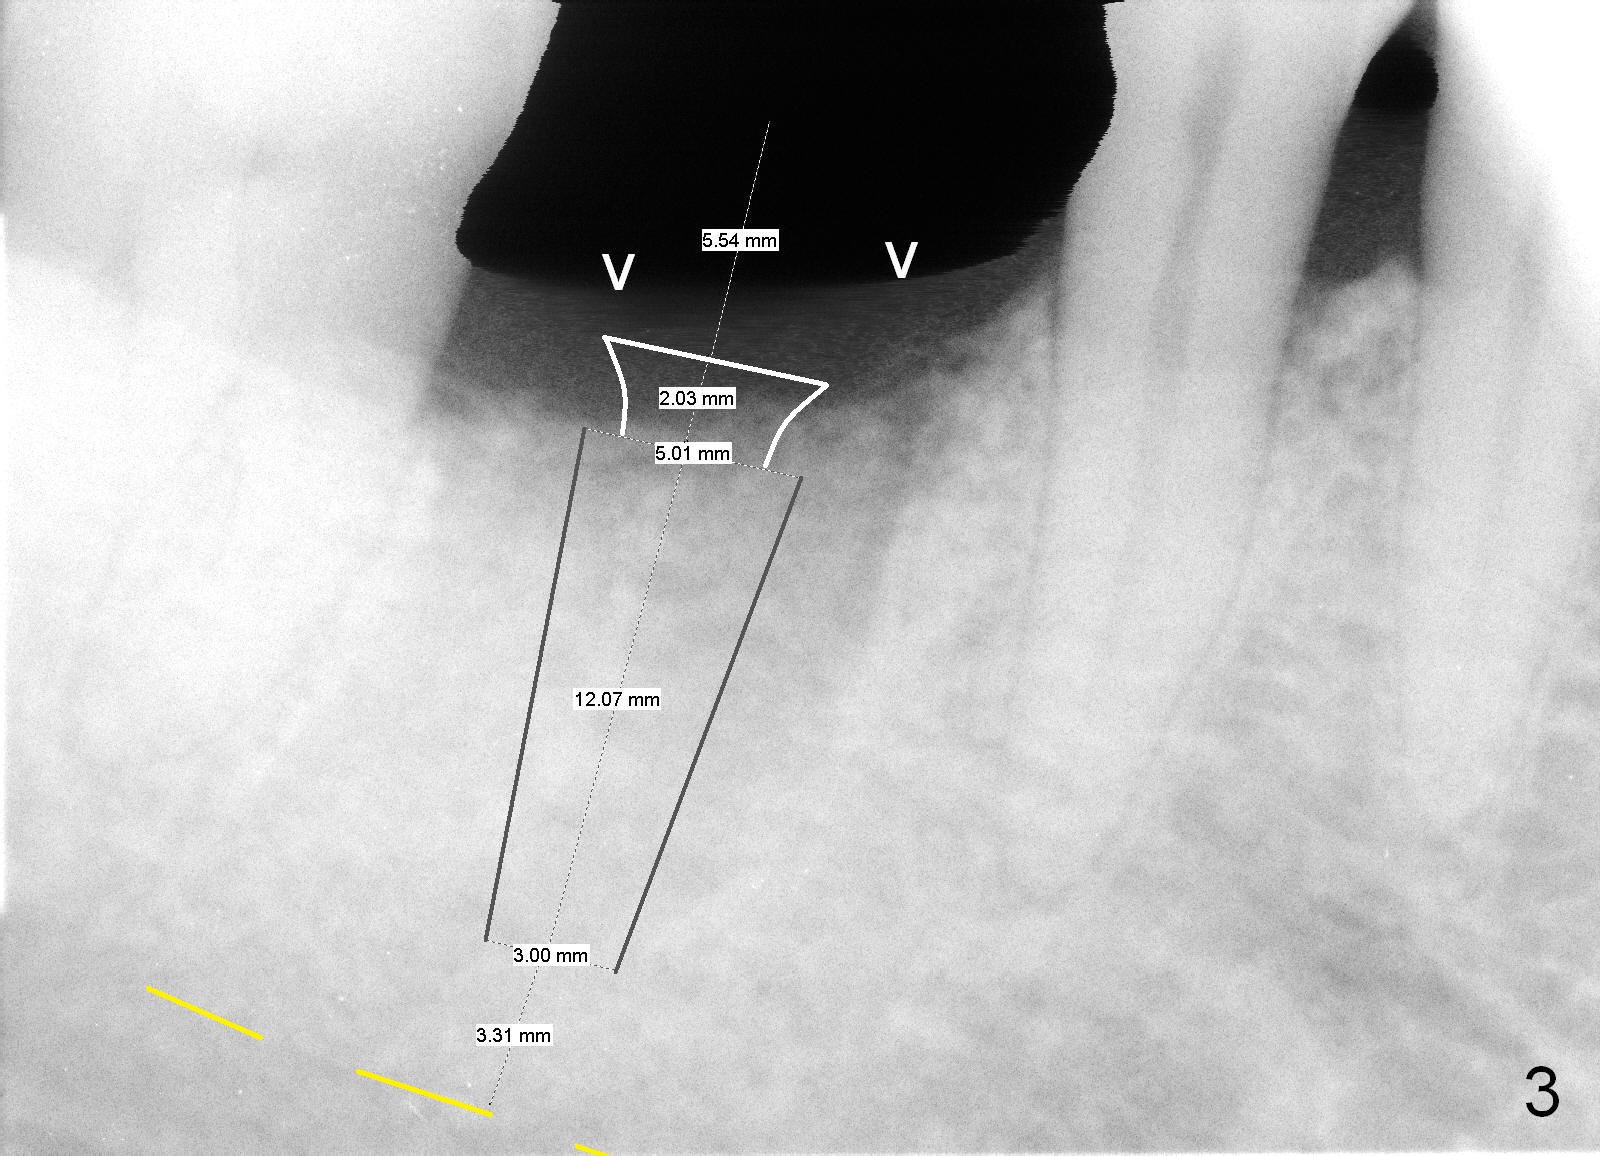

A 44-year-old man lost the tooth #30 three months ago. He is very nervous about the Inferior Alveolar Nerve (Fig.1,3 yellow dashed line). Offer Valium if needed. Check whether there is DO caries of the tooth #29 (Fig.2 <). Finish composite if indicated. There is mild to moderate buccal plate atrophy. The implant may have to be placed slightly lingually. When the insertion torque is high, place an abutment (Fig.3 white inverted cup) with subgingival margin (arrowheads: gingival margin) so that the emergency profile of the crown is better. Make an ideal immediate provisional with good emergency profile and place sutures. The mesial bone may have to be trimmed (Fig.4 red area) so that the abutment is able to be seated without interference. Take photo at each step.